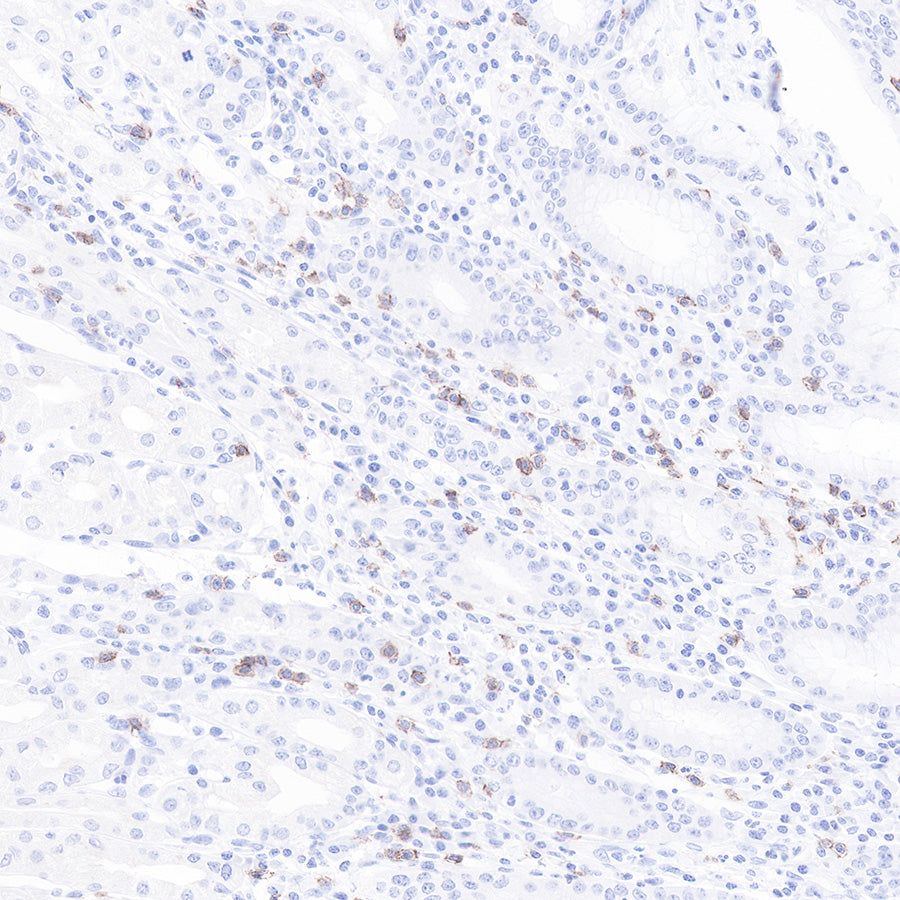

Immunohistochemistry

IHC shows positive staining in paraffin-embedded human tonsil.

CD8α Mouse mAb was used at 1/1000 dilution, followed by a Goat Anti-mouse IgG H&L (HRP) ready to use.

Counterstained with hematoxylin.

Heat mediated antigen retrieval with Tris/EDTA buffer pH9.0 was performed before commencing with IHC staining protocol.